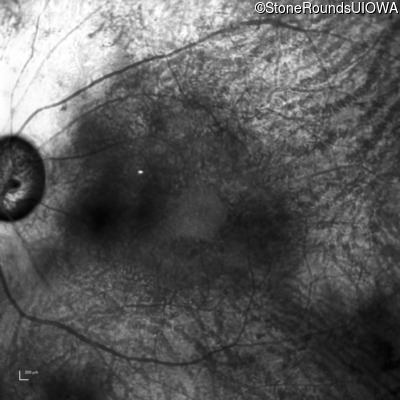

Age at visit: 62 years

OD OS

This 62 year old man had poor night vision as a teenager and developed difficulty with his peripheral vision in his early forties. His parents both grew up in the small village in Taiwan.

Diagnosis & molecular findings

Disease Gene Allele 1 variant(s) Allele 2 variant(s) Inheritance mode

AR Retinitis Pigmentosa EYS Cys2139Tyr TGT>TAT Cys2139Tyr TGT>TAT AR